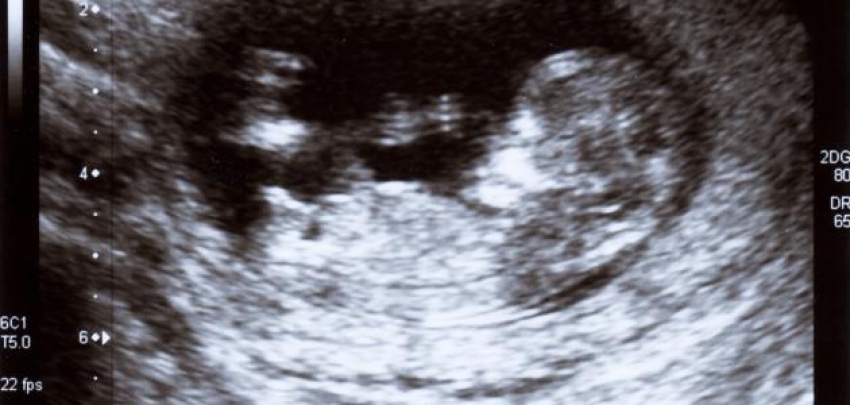

الحمل

تُعتبر مرحلة الحمل من التجارب الفريدة في حياة المرأة؛ إذ تحدث فيها الكثير من التغيُّرات لا على الجسم فقط، بل تتعدّاه إلى مزاج المرأة ومشاعرها. تحدث هذه التغيّرات نتيجةً للعديد من الهرمونات التي يفرزها الجسم استعداداً لاستقبال الجنين في الرحم، ومُساعدته على النموّ والتطوّر. من أهمّ هرمونات الحمل هرمونا الإستروجين والبروجسترون، وهما الهرمونان المسؤلان عن أغلب التغيّرات التي تطرأ على الحامل، ويزداد تركيزهما كلّما تقدّم الحمل.